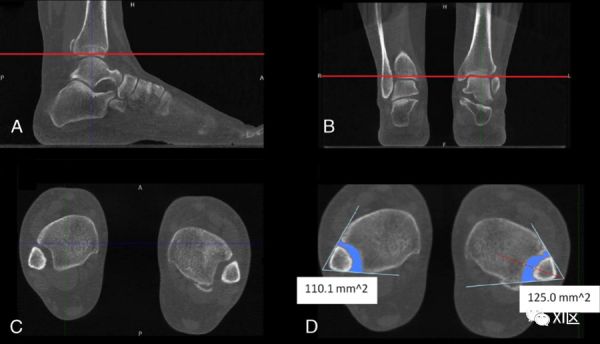

准确及时地诊断联合韧带损伤对于预防慢性踝关节不稳定和预防继发性骨关节炎至关重要。常规CT检查分析了非WB条件下的远端胫腓关节。如前所述,WB-CBCT有助于补充非WB检查的诊断产量;然而,前者的重要性尚待阐明。对于无症状的未受伤踝关节,已经表明,除了内侧间隙外,WB检查似乎在联合测量方面没有明显差异。相反,在临床怀疑有联合韧带损伤的既往踝关节损伤患者中,非WB和WB检查的平均胫腓后距离、间隔和角度测量值存在差异,观察者之间的可靠性接近完美水平。与胫骨平台附近不同水平的对侧未受伤踝关节相比,单侧联合不稳定患者的受伤踝关节显示3D容积WB-CBCT测量值增加;健康对照组中没有这种差异(图3)。

图3:一名40岁患者的WB-CBCT表现为左踝关节疼痛和肿胀。病史显示,两次受伤相隔8年,均接受保守治疗。体检显示中性愈合和足部对齐,但可能会引发一些临床操作。冠状(A)和矢状(B)视图用于确定胫骨平台上方的横向成像平面(红线)。C和D,创建2条相交线,即内侧腓骨皮质和外侧胫骨皮质切迹,有助于确定所选平面上的联合区。WB检查中,左侧联合面积为125 mm2,而对侧面积为110.1 mm2。